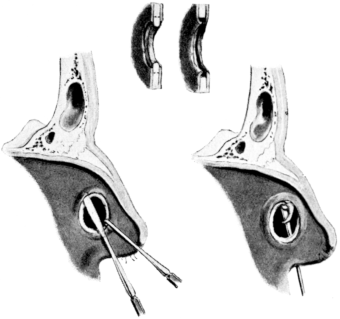

| 320. | Catheterizing the Maxillary Sinus | 626 |

| 322. | Puncturing the Maxillary Sinus | 627 |